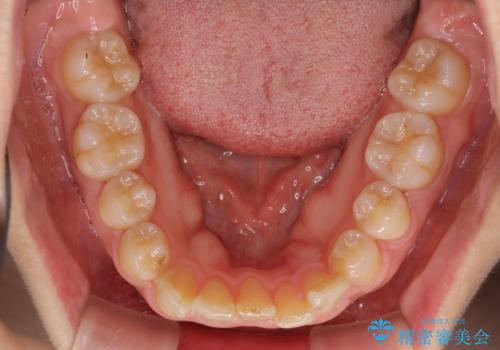

- 右上の八重歯と、左下八重歯を抜いてしまったことを気にして来院された患者様です。

下顎は既に犬歯を1本抜歯しているため、上顎右側第一小臼歯を抜歯し、ワイヤー装置にて歯列を整えることとしました。

変則的な抜歯となるため、正中と人中がずれる可能性がありましたが、仕上がりは上下正中を揃えることができました。